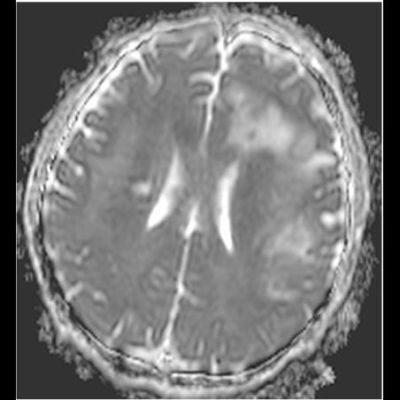

- Bilateral asimetrik subkortikal ve derin beyaz cevherde T1 ağırlıklı görüntülerde belirgin hipointens (oklar), T2A görüntülerde hiperintens (oklar), gri cevhere bakan kesimi düzgün (oklar), DAG’de hiperintens (ok) lezyonlar izlendi. Lezyonlarda T2/FLAIR uyumsuzluğu vardı (ok). Serebellar beyaz cevherde dentat nukleusu koruyan hilal işareti görüldü (ok başı). SWI sekansta sol motor kortekste hipointens kronik glioinflamatuar reaksiyon ile uyumlu sinyal değişikliği izlendi (ok başı).

- Çoğunlukla subkortikal beyaz cevherde ve U fiberlerde, asimetrik, genelde kitle etkisi yapmayan ve kontrastlanmayan demiyelinizan lezyonlar görülür. Korteks ve derin gri cevher tutulumu daha nadirdir.

- PML lezyonları, T1A görüntülerde belirgin hipointenstir. Gri cevhere bakan yüzleri keskin olup T2/FLAIR uyumsuzluğu önemli özelliğidir.

- PML lezyonlarında kronik olarak aktive olan glial hücreler ve mikroglia/makrofajlar sitoplazmalarında yüksek seviyelerde demir ve pigment içerebilir ve SWI da hipointens olarak görülür.